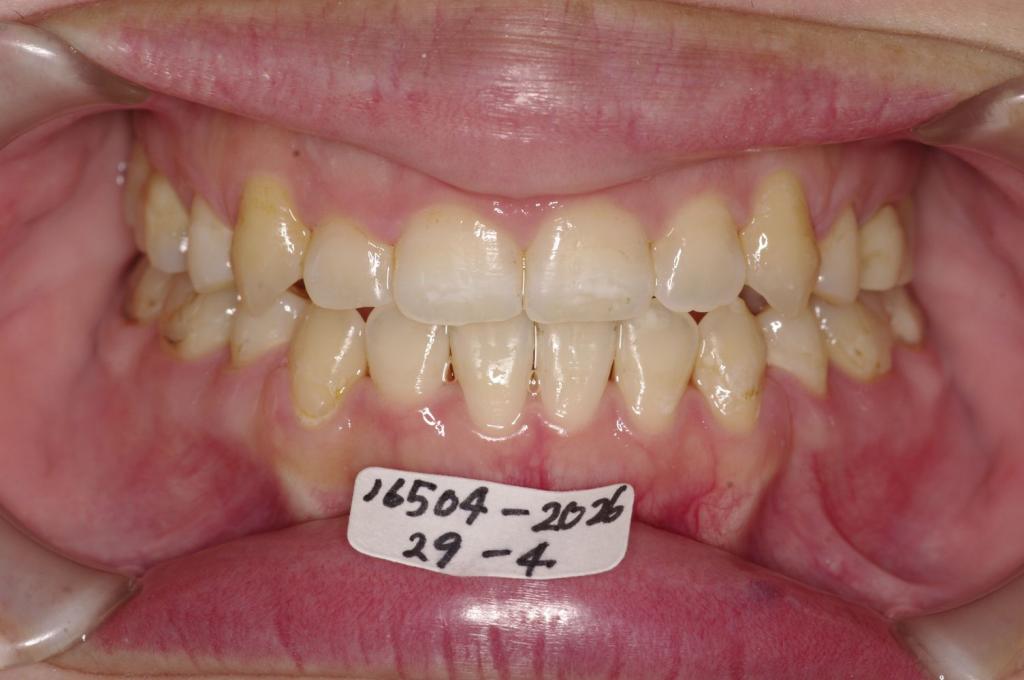

前歯、出っ歯・開咬の矯正治療

(治療期間、治療前後写真、治療方法、費用)WORKS